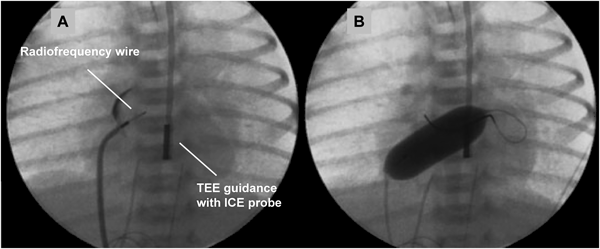

通常のBASが困難,危険,無効な状況としては,肥厚した心房中隔壁,intact atrial septum(IAS),小さいLA,低体重児,両側FVの閉塞・IVC離断などがある.肥厚した心房中隔壁に対して以前はblade atrial septostomyが施行されたが,心房壁や右室流出路(RVOT)の裂傷から死亡する合併症があり,近年はあまり施行されなくなっている2,3).これに対してballoon atrial septal dilationは効果がやや劣るが安全に施行できる.有効な欠損孔を得るためには新生児でも10~12 mm径のバルーンが必要である4,5).inflation/deflationが素早くできるArmada(12 mm×20 mm; Abot)などが適している.当院での経験になるが,Balloon atrial septal dilationにBASを組み合わせることで十分な効果が得られている.IASに対して日本では昨年までBrockenbrough needleを使用せざるを得なかった.新生児・乳児の体格でも心房中隔穿孔は不可能ではないが,特にHLHSでは心房中隔壁が厚く,それを穿孔するだけのLA容積(奥行き)がない場合が多く(Fig. 2),心房壁の穿孔・心タンポナーデの合併率が高くなる6,7).欧米では10数年前からradiofrequency wireを用いた心房中隔穿孔が施行されている(Fig. 3)8).心房中隔に接触させて通電するだけで中隔を穿孔できるので,LAが小さい新生児の肥厚したIASでもより安全に穿孔できる.日本でも2014年8月からNykanen RF wireが使用可能となった(Fig. 4).このwireの直径は0.024″,長さは265 cmで,先端のActive atraumatic tipの直径は0.016″,長さは1.5 mmである.Active tip以外の部分は整形が可能である.Connector cableでGeneratorと接続し,5~10 W,1~10 secの通電で組織の穿通が可能である.現在日本ではPA IVSの肺動脈弁穿孔とIASの心房中隔穿孔に適応があり,その使用には講習が必要である.肥厚した心房中隔のためにBASが無効の場合にはstent septostomyも有効である.留置後抗血小板薬だけでは血栓形成の報告があることから抗凝固療法が必要と思われる9).またstent migrationの報告や強度の内膜増殖を来す期間が不明であり,注意を要する10).

TEE, transesophageal echocardiography; ICE, intra-cardiac echocardiography.

Wire: outer diameter 0.024″, length 265 cm; Active tip: diameter 0.016″, length 1.5 mm.